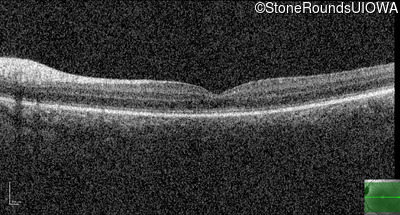

Optical Coherence Tomography - Right - 10/200

Exemplar / OCT Stack

Optical Coherence Tomography - Left - 10/100